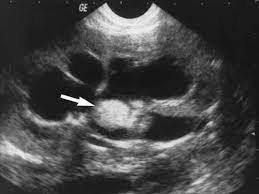

This picture shows the “Ball on tree” appearance of Medullary type RPN

https://www.ctisus.com/responsive/learning/exhibit/genitourinary/311982